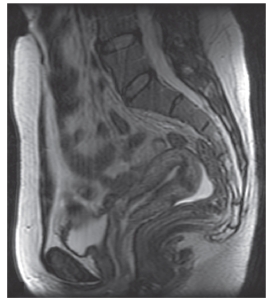

Study this image.Identify the imaging plane and modality.

A) MRI,sagittal

B) CT,sagittal

C) MRI,axial

D) CT,axial